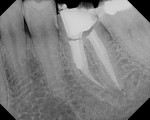

A 34-year-old female presented with pain to the dental office. A root canal had been performed 3 months ago by a general dentist. Previous endodontic treatment with acute apical periodontitis was the diagnosis. The patient did not exhibit swelling. She reported taking over-the-counter pain medications but no antibiotics. She had no contributory medical history. Clinically, a crown was present but no visible redness or inflammation around the gingiva. Radigraphically, root canal treatment was evident, with a separated file in the middle of the mesiobuccal (MB) root, short fills on the mesial and distal roots, and a missed distal canal. Periapical lesions were present at the apex of the mesial and distal roots (Figure 4).